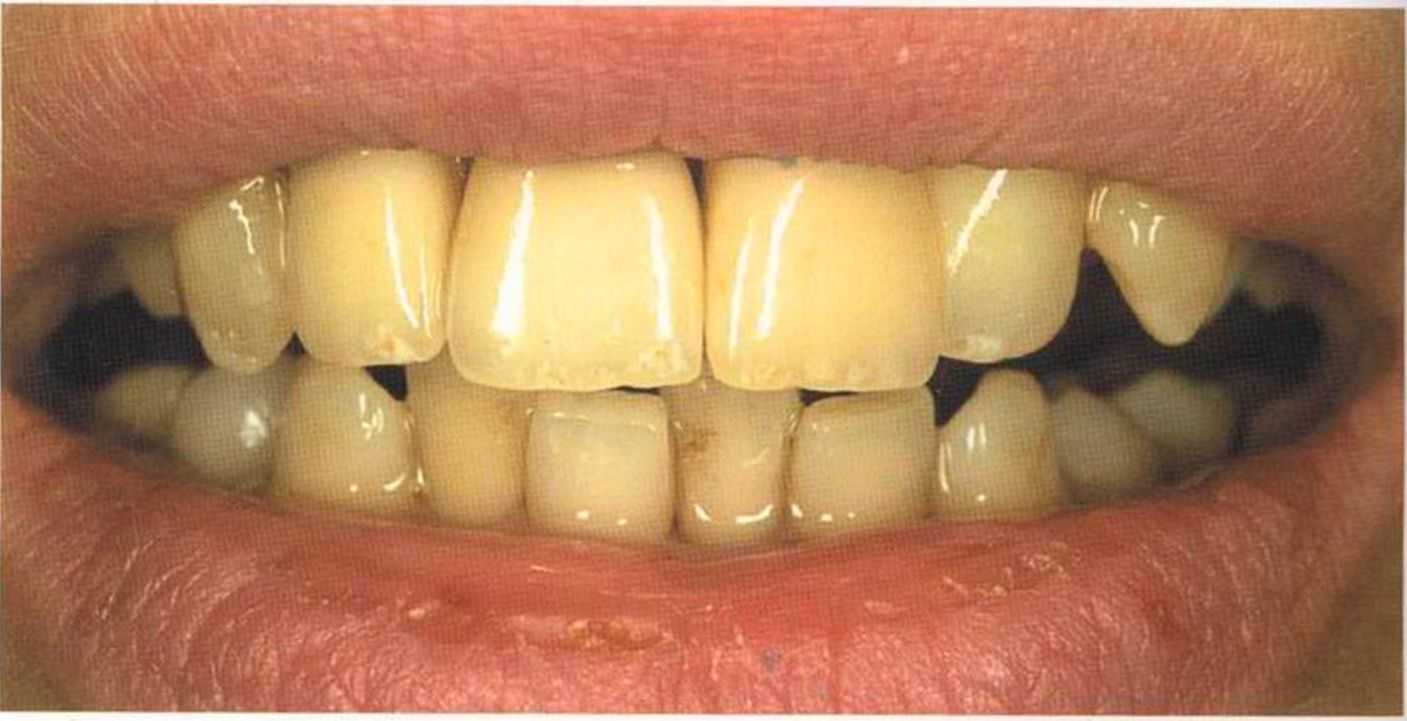

Вспомним, как все начиналось.

Первое лечение проходию много лет назад у другого доктора. Со временем ос те пи / ка уху дин ьась, особенно в пришеечной области. Этот пациент хотел новые коронки в области 12 и 22, по сомневсься, нас кол ько хорошо они будут выглядеть.

Результат с использованием In-Ceram развеял все сомнения, и решение об изготовлении коронки на другой боковой резец не заставило себя долго ждать.

После того как мы определит цвет зуба, решено быо сначсьа изготовить одну коронку.